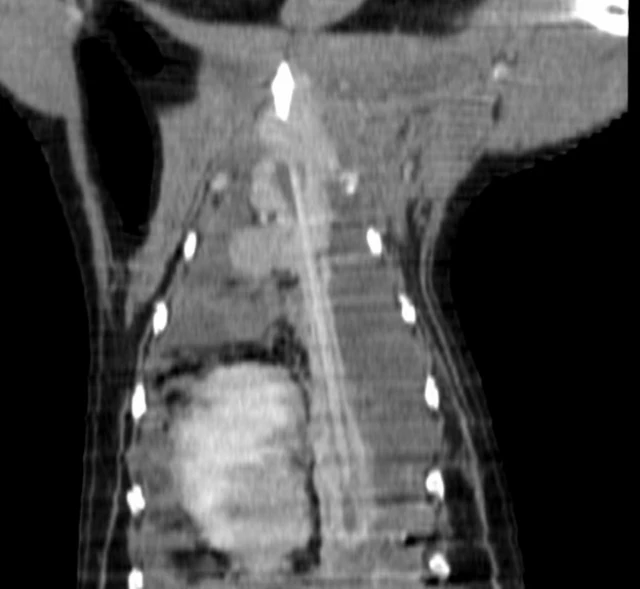

Veterinerler bu defa köpeğe röntgen çektirdi: 20 cm uzunluğundaki bir kebap şişi karşılarında duruyordu.

Bessie'nin ameliyatını yapan veteriner Henry L'Eplattenier, "Şişin göğse kadar gidip hayati organlardan geçmemiş olması bir mucize. O çok şanslı bir köpek" diye konuştu.

Şişin yemek borusundan zamanla göğse taşındığı ve orada takıldığı düşünülüyor.